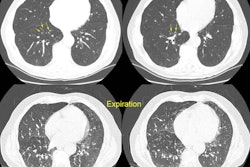

Right Pneumothorax

The female patient shown below presented with shortness of breath and right sided pleuritic chest pain. The chest radiograph demonstrated a large right pneumothorax with compressive atelectasis of the right lung. Despite chest tube placement, the pneumothorax persistent and the patient required thoracoscopic surgery for apical blebs.